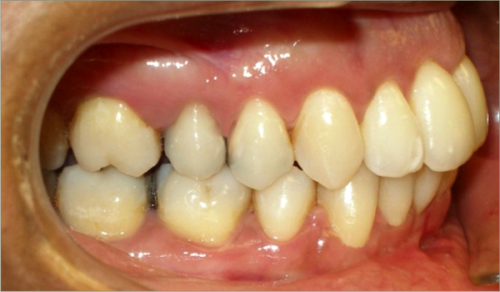

32 year old female:

Diagnosis:

- Previously lost upper first molars

- Severe lower arch crowding

- Midline discrepancy

- Narrow upper arch form

Treatment:

- Extraction of lower right first bicuspid

- Substitution of upper second molars for first molars

- Full fixed appliances

- 23 months